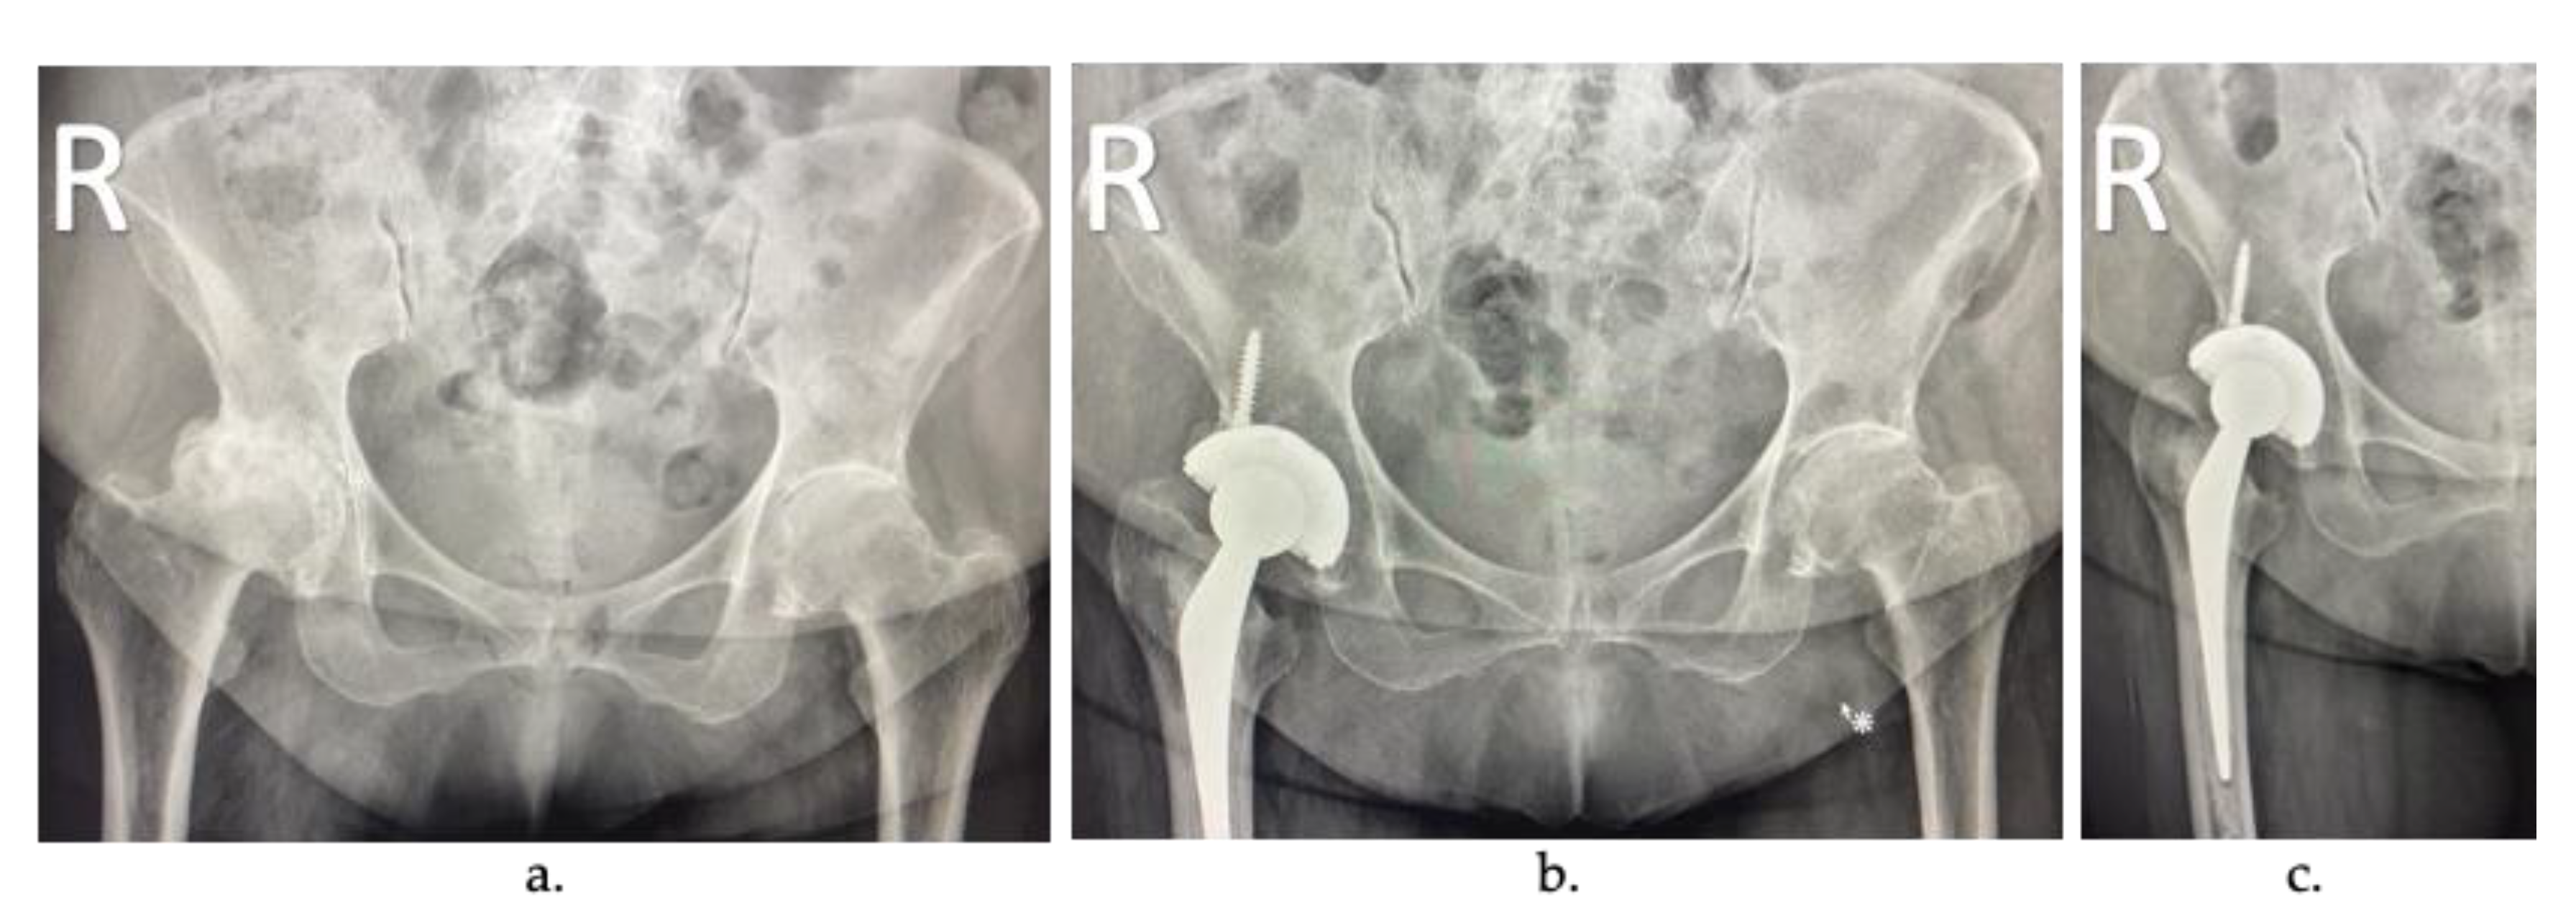

In total joint replacement (TJR), also known as arthroplasty, the diseased or damaged parts of the joint are removed (Figure 2a) and replaced by prostheses or implants (Figure 2b). TJR can be performed on various joints, including the hip, knee, ankle, shoulder, elbow, fingers, and wrist. However, hip and knee prostheses are the most common [10].

Figure 2.

Arthroplasty radiographs: (a) patient with severe osteoarthritis in the right hip, (b) joint replacement of the femoral component, and (c) cemented joint replacement.

During TJR, the most common method of fixing the implant is with a load-transfer material’s introduction, typically an acrylic bone cement (ABC) (Figure 2c), introduced into the space between the implant and the joint as a flow-able mixture that eventually hardens over time [11]. The main advantage of these cemented joint replacements is the reduction in the recovery time of the surgery. Once polymerized, the cement can support a load and offer immediate stability, and it has shown excellent long-term results [12]. However, if the cement layer is loosened, the surrounding bone can be reabsorbed, and implant failure can eventually occur. Today, acrylic bone cements use is around 90% of total hip replacement (THR) surgeries in developed countries such as the United Kingdom, the Netherlands, and France.